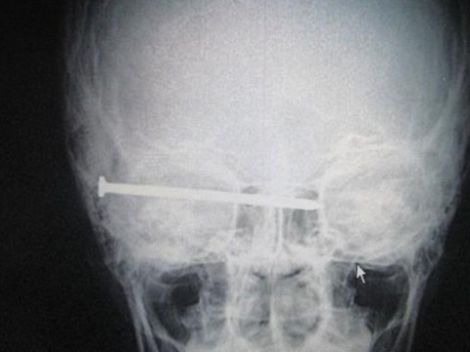

Najstniški samomorilec si je v glavo zabil dolg žebelj in preživel